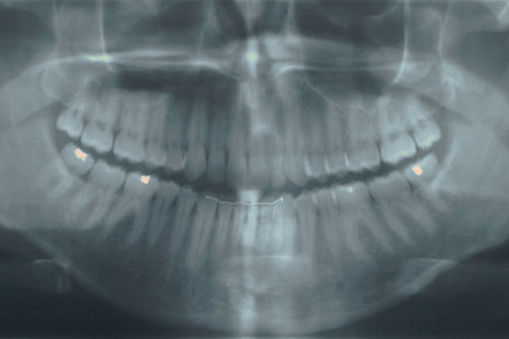

Hiện nay có thể sử dụng X-quang nha khoa để dự đoán ai là người có nguy cơ gãy xương, một nghiên cứu mới của các nhà khoa học tại Học viện Sahlgrenska được đăng trên Tạp chí Nature Reviews Endocrinology.

Các nhà nghiên cứu Gothenburg có một bước xa hơn với một nghiên cứu mới cho thấy rằng có thể sử dụng X-quang nha khoa để kiểm tra cấu trúc xương ở hàm dưới và cũng để dự đoán ai là người có nguy cơ gãy xương trong tương lai. Kết quả nghiên cứu này đã được đăng trên Tạp chí Xương và cũng đã được đề cập đến trong cả hai tạp chí Nature Reviews Endocrinology và Tạp chí Phố Wall.

Grethe Jonasson, nhà nghiên cứu tại Trung tâm nghiên cứu của các dịch vụ nha khoa công cộng ở Vastra Götaland, người khởi xướng nghiên cứu gãy xương, đã nhận định: “X-quang nha khoa có chứa rất nhiều thông tin về cấu trúc xương. Bằng cách phân tích những hình ảnh này, nha sĩ có thể sớm xác định những người có nguy cơ gãy xương trong thời gian dài trước khi gãy xương đầu tiên xảy ra."